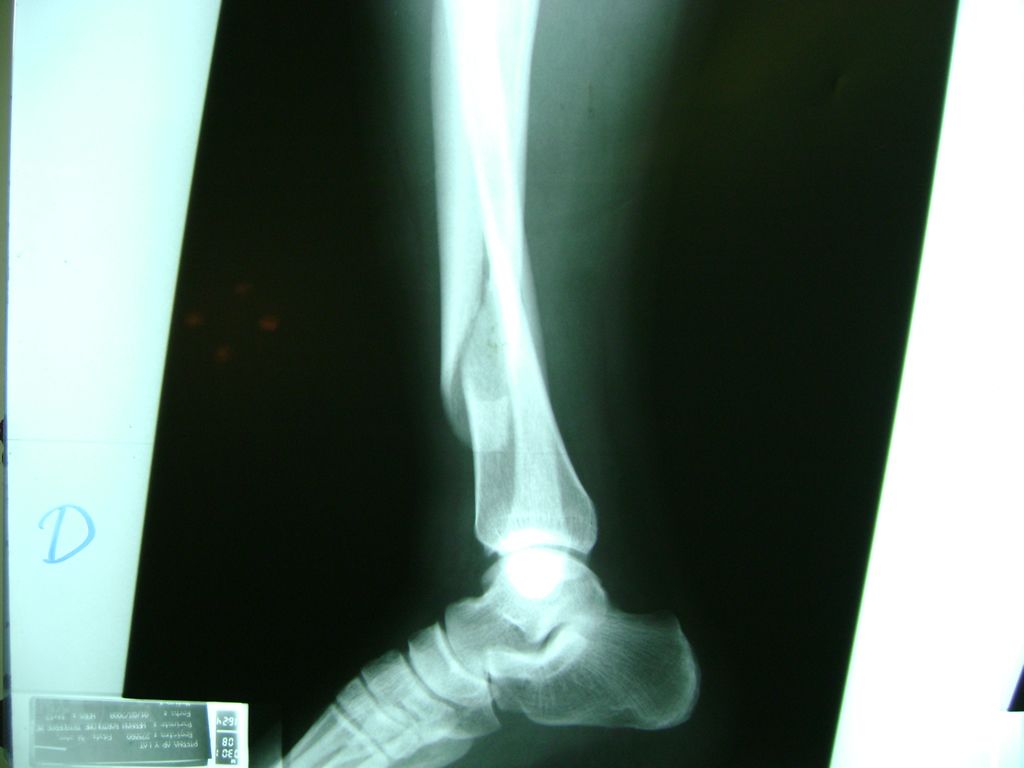

Calcaneo - Perone y Tibia

La mayor parte de las roturas implican a la parte proximal del hueso (parte del hueso próximo a la rodilla) o a la parte distal (parte del hueso cerca del tobillo).

Debido a la fina cobertura de piel que recubre la tibia y el peroné, las fracturas generalmente son abiertas, es decir, el hueso roto rasga la piel, atravesándola. Las fracturas de tibia y peroné generalmente se producen por un fuerte impacto o torsión.